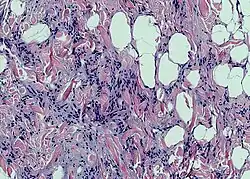

Photomicrograph of a spindle cell lipoma. | |

According to histology, the lesion is made up of tiny, homogeneous spindle cells and mature adipocytes combined with eosinophilic collagen bundles inside a myxoidstroma. According to immunohistochemical staining, the spindle cells are positive for CD34 but negative for S-100 protein.[3]